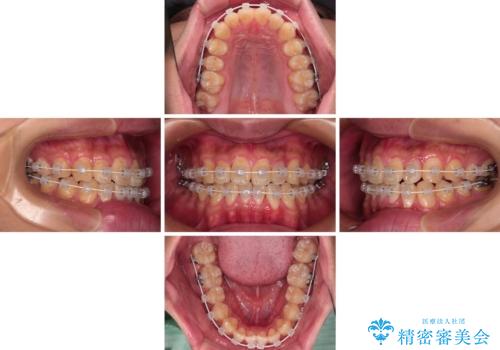

クロスバイトはありましたが、叢生の程度としては酷くなかったため、ワイヤー矯正でもマウスピース矯正でも、好きな方を選択していただきました。

一日中マウスピースを装着する煩わしさから、マウスピース矯正を継続する自信がないとのことで、ワイヤー装置にて矯正治療を行うこととしました。

気になっていたクロスバイトは速やかに改善され、1年間で治療を終えることができました。

治療開始前は汚れが多く、全体的に歯肉が腫れていましたが、矯正治療を通して腫れも少しずつ改善されました。